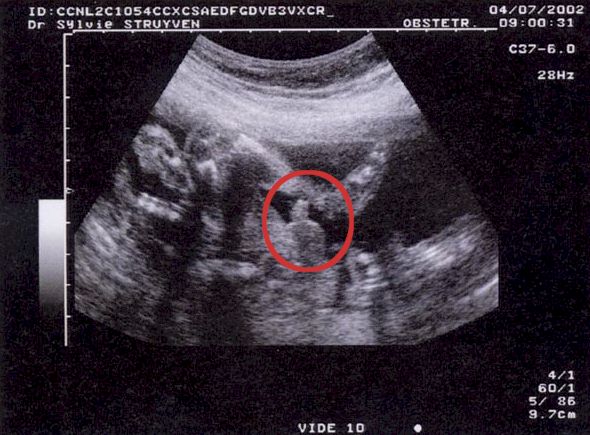

2nd Echographie obstétricale -